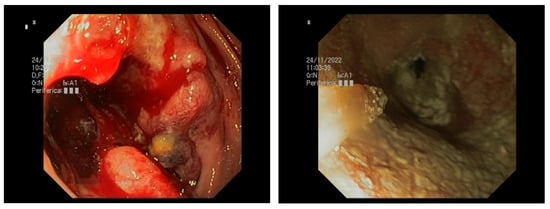

4.2. Is HP a Possible Gold Standard in Malignancy-Related NVUGIB?